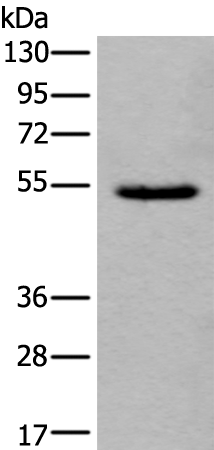

分类: 科研抗体货号: P04309别名: SAPK4; PRKM13; MAPK 13; MAPK-13; p38delta应用: WB,IHC反应种属: Human, Mouse, Rat